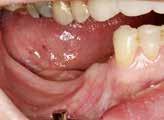

Implantatindsættelse i den atrofiske posteriore mandibel kan være umulig eller vanskelig som følge af reduceret afstand fra toppen af processus alveolaris til den øvre begrænsning af canalis mandibulae. Indsættelse af korte implantater, vertikal knogleopbygning før implantatindsættelse ved hjælp af sandwich-osteotomi, onlay bloktransplantat og alveolær distraktions-osteogenese eller lateralisering eller transpositionering af n. alveolaris inferior med samtidig indsættelse af standardlængde implantater er de hyppigst anvendte kirurgiske teknikker til protetisk rehabilitering af den atrofiske posteriore mandibel. Behandlingsstrategien afhænger primært af processus alveolaris’ højde samt afstanden fra toppen af processus alveolaris til den øvre begrænsning af canalis mandibulae. Kendskab til de forskellige behandlingsmetoder og begrænsninger er derfor vigtigt i forbindelse med planlægning og udførelse af implantatbehandling i den atrofiske posteriore mandibel for at opnå et forudsigeligt og holdbart behandlingsresultat med mindst risiko for komplikationer.

Formålet med nærværende temanummer er at præsentere den nuværende viden om principperne for behandlingsplanlægning med fokus på den radiologiske undersøgelse samt valg af relevant behandlingsstrategi i forbindelse med protetisk rehabilitering af den atrofiske posteriore mandibel. Indledningsvis omtales de ge-

nerelle aspekter for behandlingsplanlægning. Herefter beskrives den nuværende viden om protetisk rehabilitering med korte implantater. De kirurgiske teknikker til vertikal knogleopbygning før implantatindsættelse ved hjælp af sandwich-osteotomi, onlay bloktransplantat og alveolær distraktions-osteogenese vil blive beskrevet i de efterfølgende artikler. Afslutningsvis redegøres for lateralisering eller transpositionering af n. alveolaris inferior med samtidig indsættelse af standardlængde implantater.